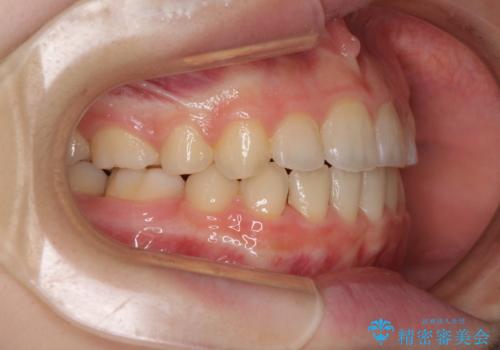

- 八重歯と乳歯が残っていることを気にして来院された患者様です。

乳歯が3歯残っており、下顎は左右ともに後続永久歯がない状態でした。

口元が突出しており、口が閉じにくかったため、乳歯を含め上下5歯を抜歯して矯正治療を行うこととしました。

下顎の乳歯は永久歯と比べて幅が大きいため、抜歯した場合のスペースが大きく、治療には長期間を要することが一般的です。

今回の患者様は中学生ということもあり、成人の患者様と比べ動きが速く、2年間で治療を終えることができました。